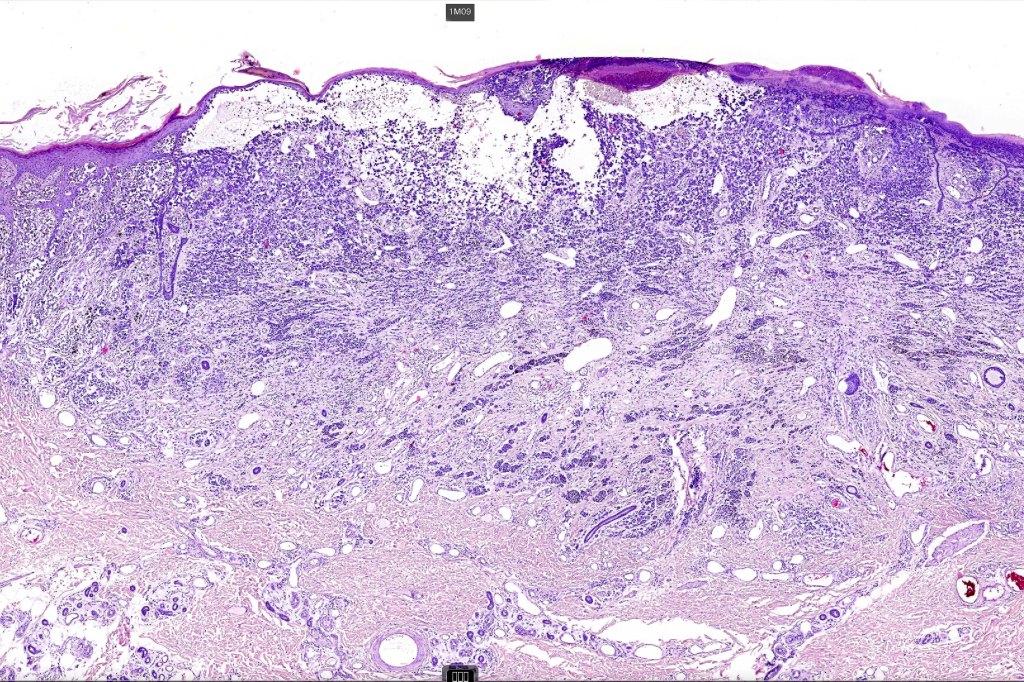

An exceedingly rare variant of melanoma. The term includes cases of melanoma that show features of an associated inherited bullous dermatosis such as epidermolysis bullosa or acquired immunobullous intraepidermal or sub epidermal bullous dermatosis such as pemphigus or bullous pemphigoid and cases where the blister develops directly overlying the melanoma in the absence of any underlying/associated blistering condition. It is generally recommended that measurement of the melanoma should be from taken below the blister/vesicle so as to avoid over-estimating tumor thickness.

Case courtesy of Dr. Antonina Kalmykova